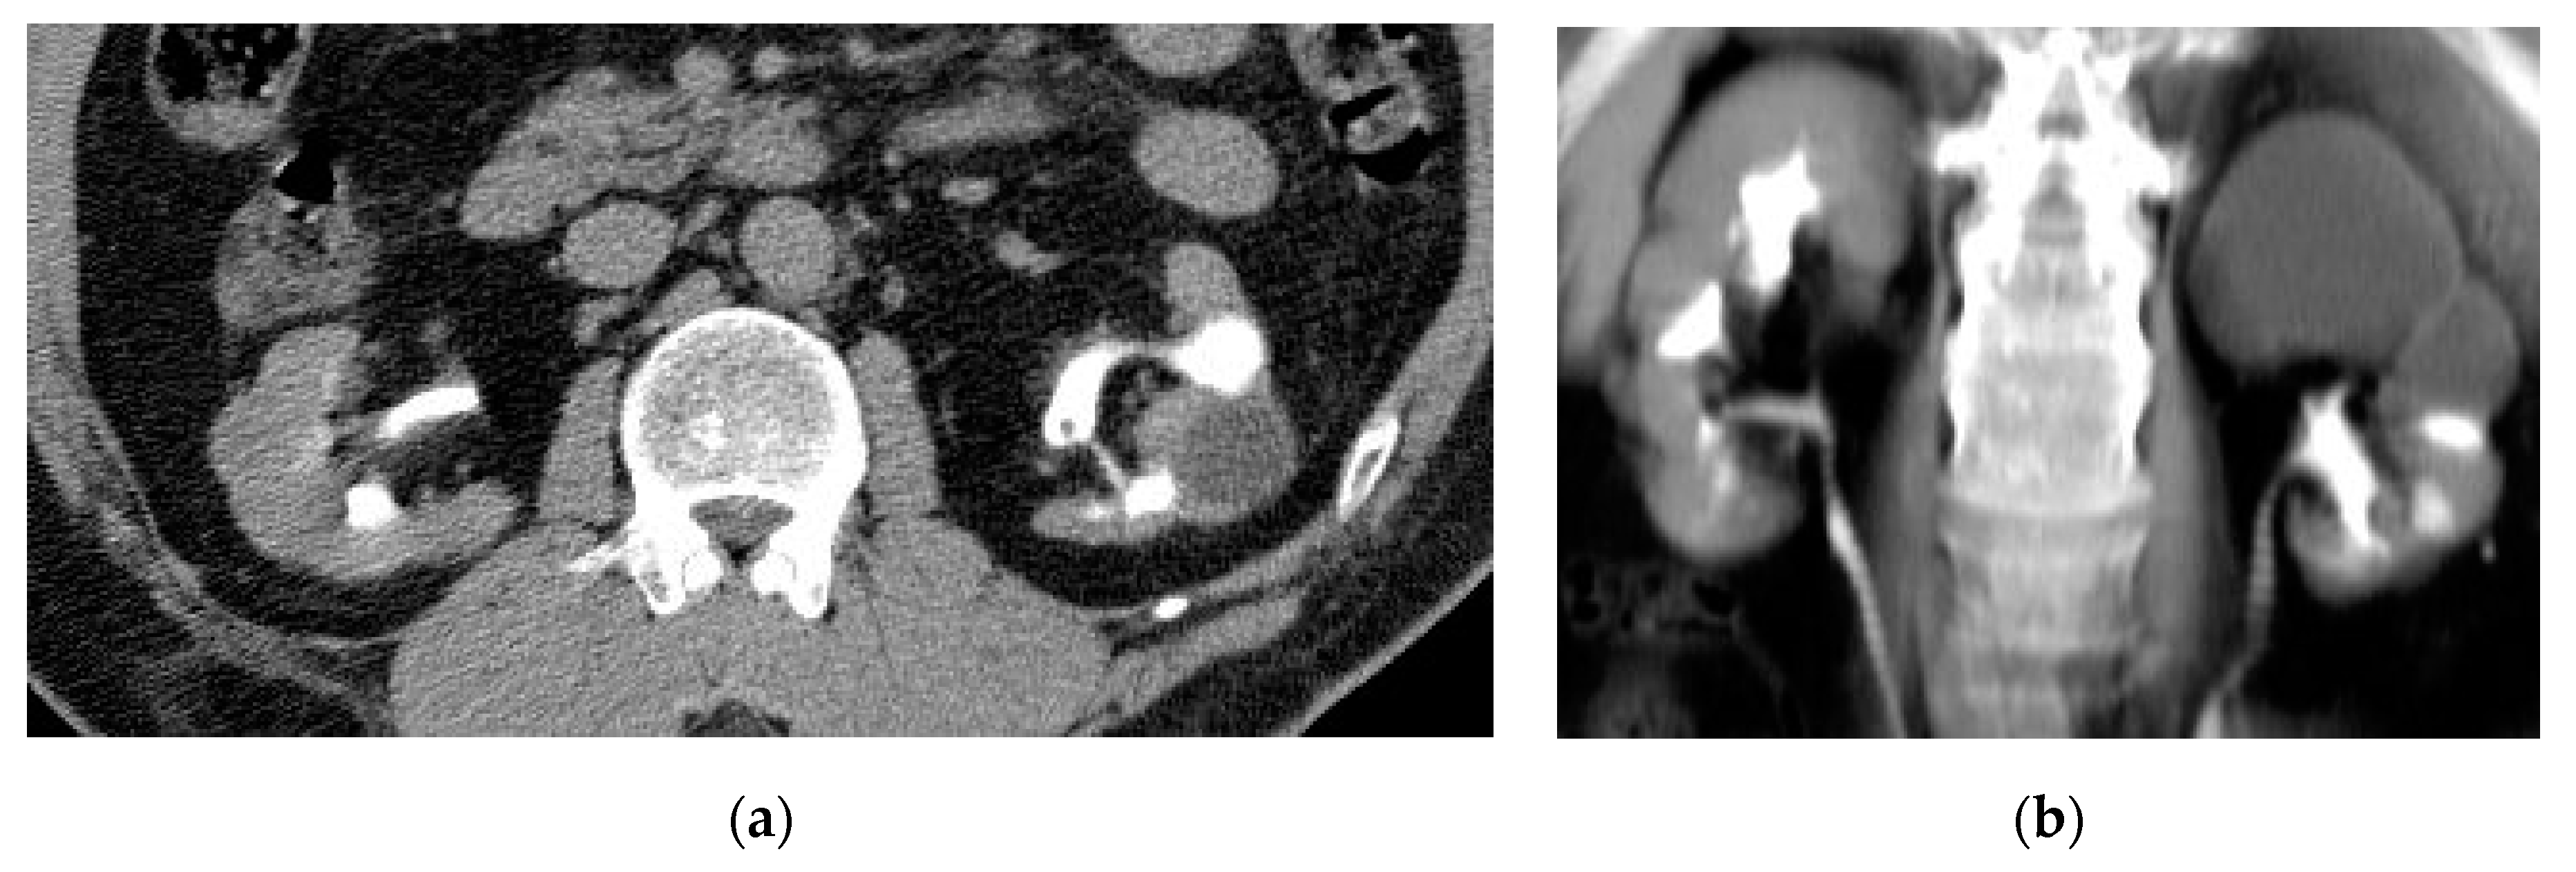

2.5. Xanthogranulomatous Pyelonephritis (XGP)

| Xanthogranulomatous Pyelonephritis | Non-functioning enlarged kidney, obstructing stone within a non-dilated renal pelvis, expansion of the calyces, and inflammatory changes in the perinephric fat. |